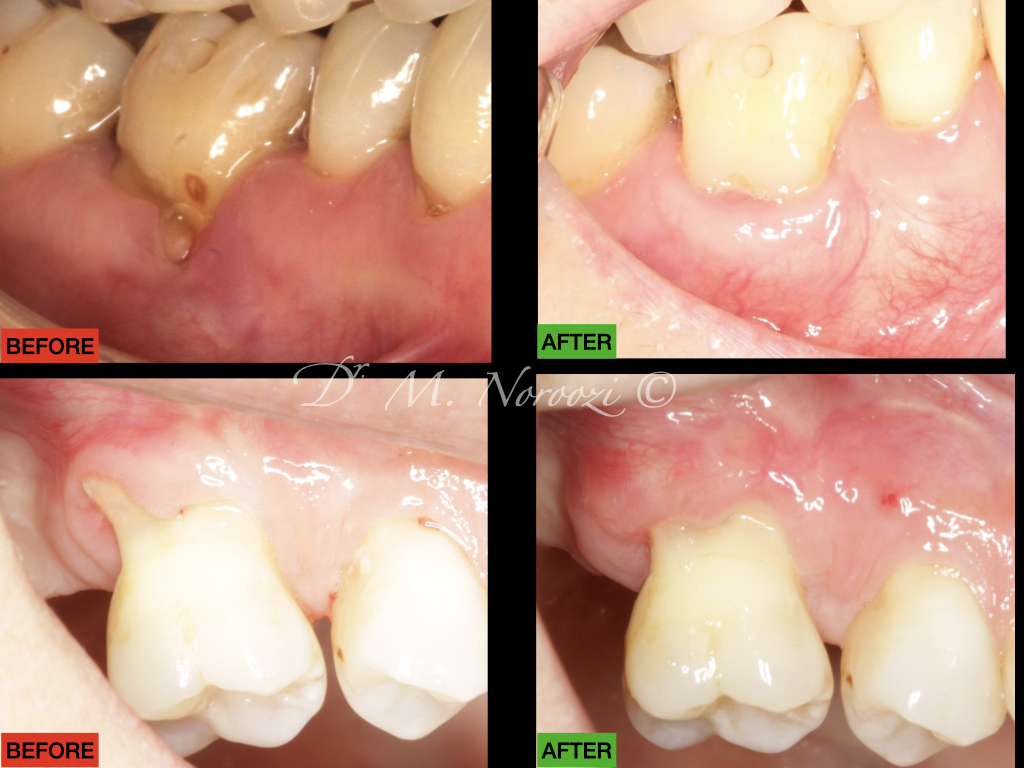

Connective Tissue Gingival Grafting for Gingival Recession